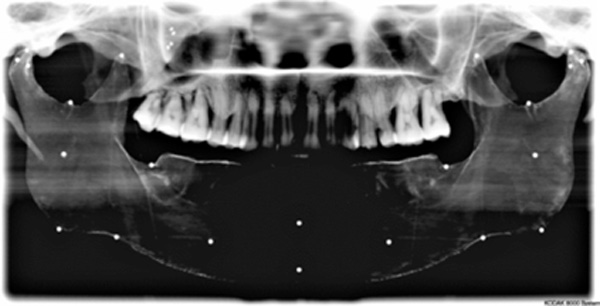

Cephalometric image of experimental model showing rapid prototype geometry and markers.

Experimental models were imaged or scanned using digital panoramic, cephalometric and cone beam computed tomography; geometric features and markers were clearly visible in all images. An example is provided in (Fig. 17).